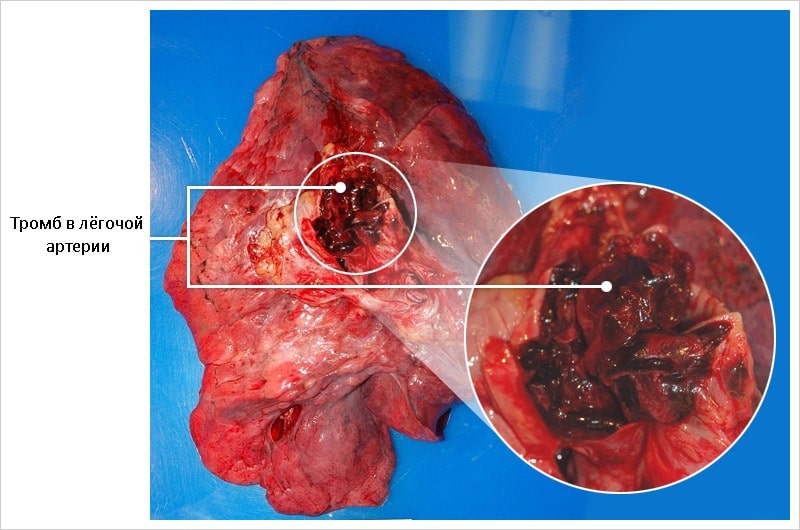

Тромб в лёгочной артерии, результаты вскрытия